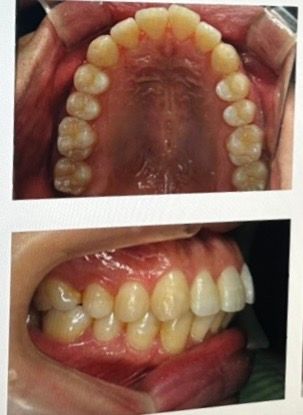

발치 교정이 필요한지 진단받고 싶어요

1. 돌출의 정도가 심한 편인지

2.외모적 관점말고 건강 관점에서 발치교정이 도움이 될지

어금니나 견치 교합은 상대적으로 안정된 상태인 반면, 앞니 돌출이 심한데 이런 경우 앞니를 집어넣기 위한 공간이 부족해 발치교정이 우선고려될 것 같습니다.

외모적 관점에서는 발치 교정 후 광대가 푹 파였다고 느끼는 경우가 종종 있습니다. 건강 관점에선 당연히 발치보다는 비발치가 덜 침습적입니다만 그 외 방법이 없다면 빼는 거고요.